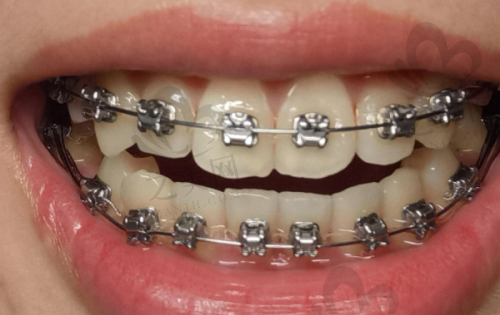

山西阳泉庆鸿口腔是当地的高人气口腔诊疗机构,作为该地区口腔保健领域的佼佼者,以其可靠的服务和新型的技术吸引了众多患者的青睐。这里拥有一支团队,团队成员均具备扎实的专科知识和一定的临床经验,能够为患者提供个性化的口腔诊疗方案,无论是常规的洁牙、牙齿矫正等都能胜任。